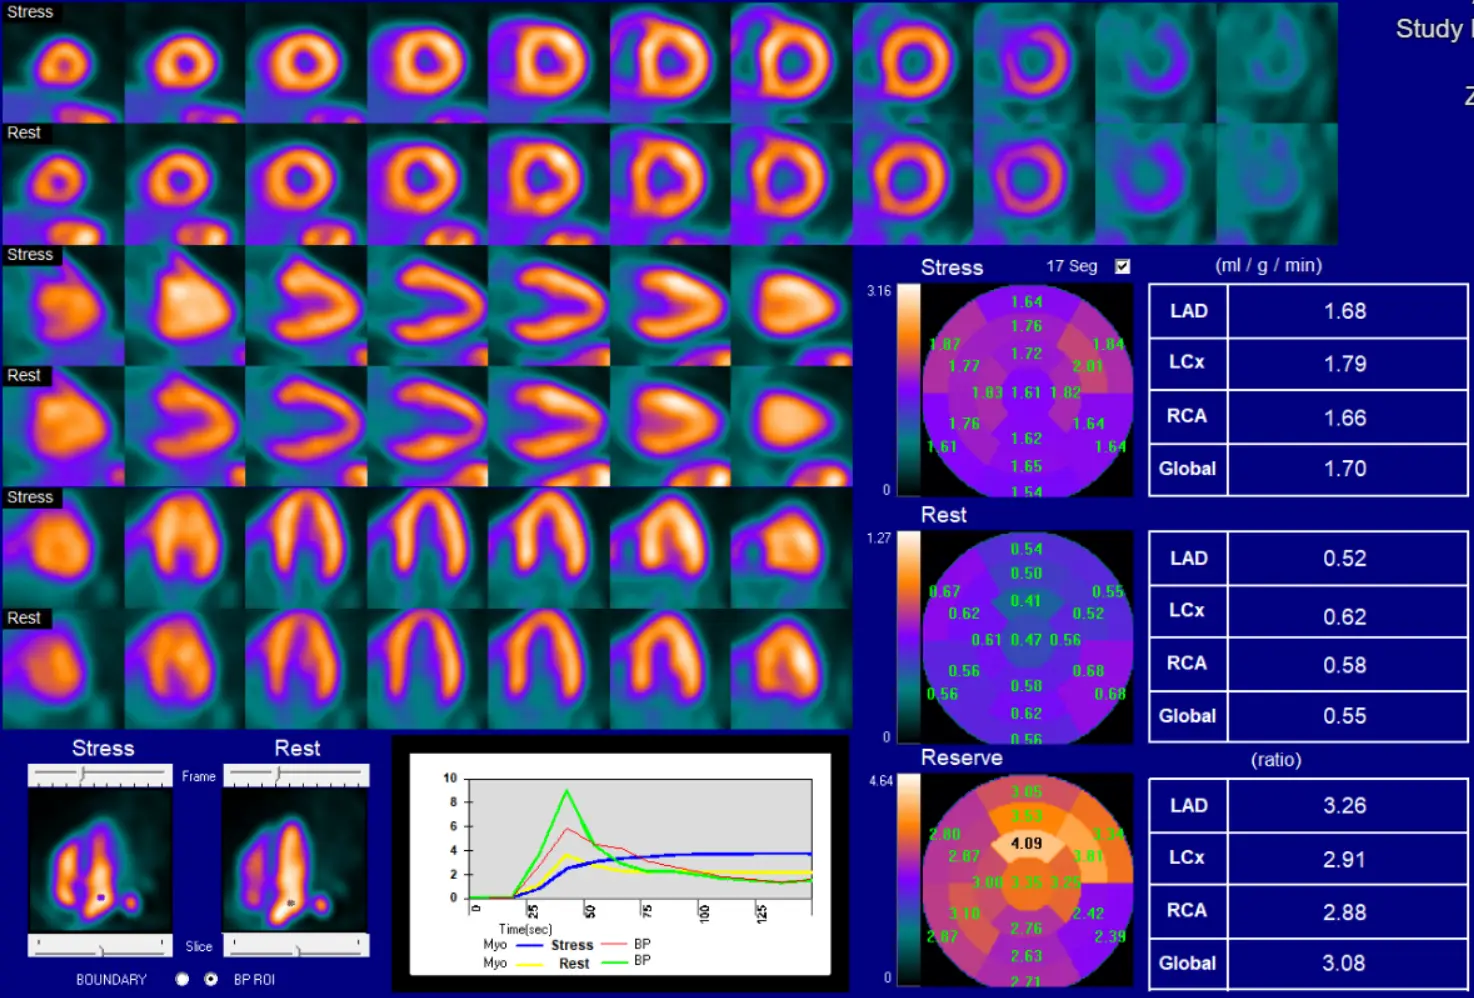

Example of Splenic Shutoff without Perfusion Defects

57-year-old male with hypertension, diabetes mellitus, and chronic kidney disease who presented for the evaluation for suspected CAD. A PET-MPI imaging revealed normal relative regional with no identifiable perfusion defects. (B) However, albeit a normal resting myocardial blood flows, the patient’s stress myocardial blood flow remained unchanged following the administration of regadenoson with a severely reduced myocardial flow reserve of 1.09. Assessing the patient’s hemodynamic responses, we can also note an unchanged heart rate (75 bpm rest vs 76 bpm stress) and failure to observe expected EF enhancement (36% at rest vs 37% at stress). The patient’s coronary artery calcium score (6246) only served to increase the concern for CAD. (C) Inspection of the spleen (white arrows) reveals a failure to exhibit visual signs of splenic switch-off (SRR was 1.1). Based on these findings, the patient was recommended to obtain an invasive catheterization due to growing suspicion of non-response to regadenoson. D ICA revealed a significant obstructive coronary artery disease LAD (Left Anterior Descending) lesion (yellow arrow) 1